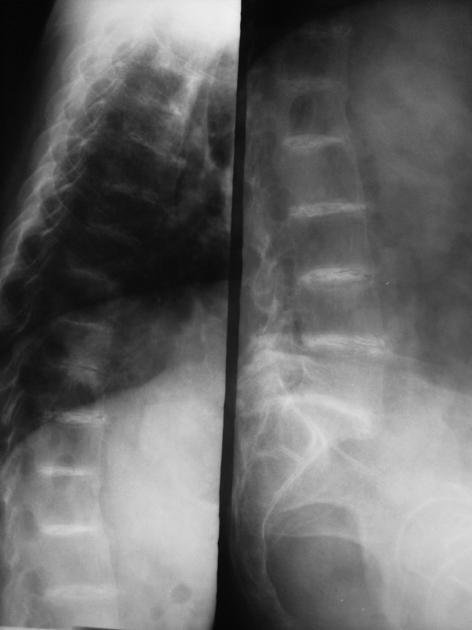

Ochronosis